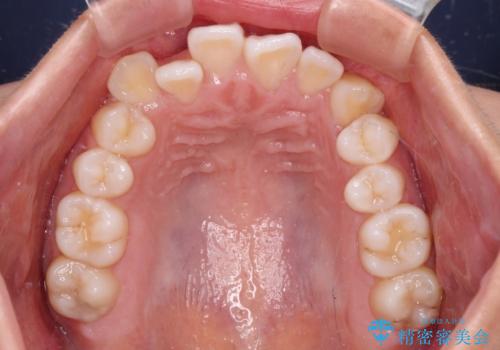

前歯のデコボコを楽して改善 ワイヤー装置による矯正治療

- 前歯のデコボコを治したいとのことで来院された患者様です。

インビザラインによるマウスピース矯正も適用となる歯列でしたが、できる限り楽して、短期間で治したいとのことで、ワイヤー装置にて矯正治療を行うこととしました。